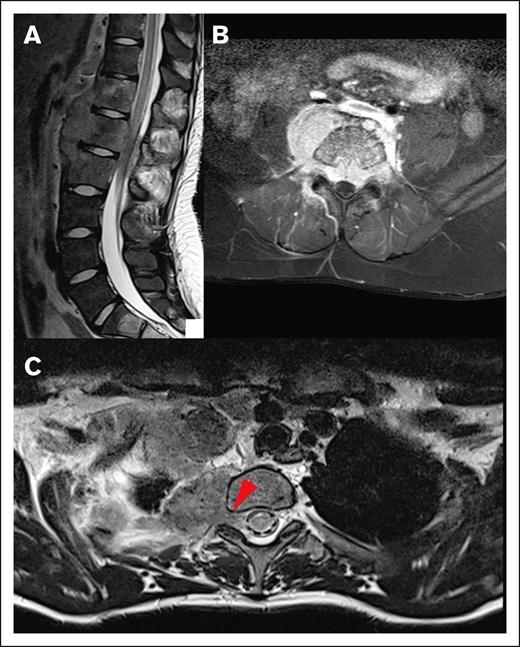

Most lesions (92.7%) extended through the neural foramina of either the vertebrae or sacral bone; 2 lesions did not extend through the neural foramina, and 2 lesions could not be evaluated (Figure 4). Thirty-one lesions entered the spinal canal. Of these, 54.8% caused displacement of the spinal cord, 25.8% were adjacent to the spinal cord but did not cause displacement, and 19.4% did not contact the spinal cord (Figure 5). None of the lesions infiltrated into the spinal cord itself. Spinal cord edema was evaluated for patients who had MRI available (17 of 31 lesions). Among these evaluable lesions, only 12.9% had evidence of spinal cord edema.

Local impact on CNS structures. (A) Displacement and mild compression of spinal cord to the right without contrast enhancement in the transverse T1 fat saturated image. (B) The same patient with edema clearly visible in the spinal cord in a sagittal T2-weighted MRI image.